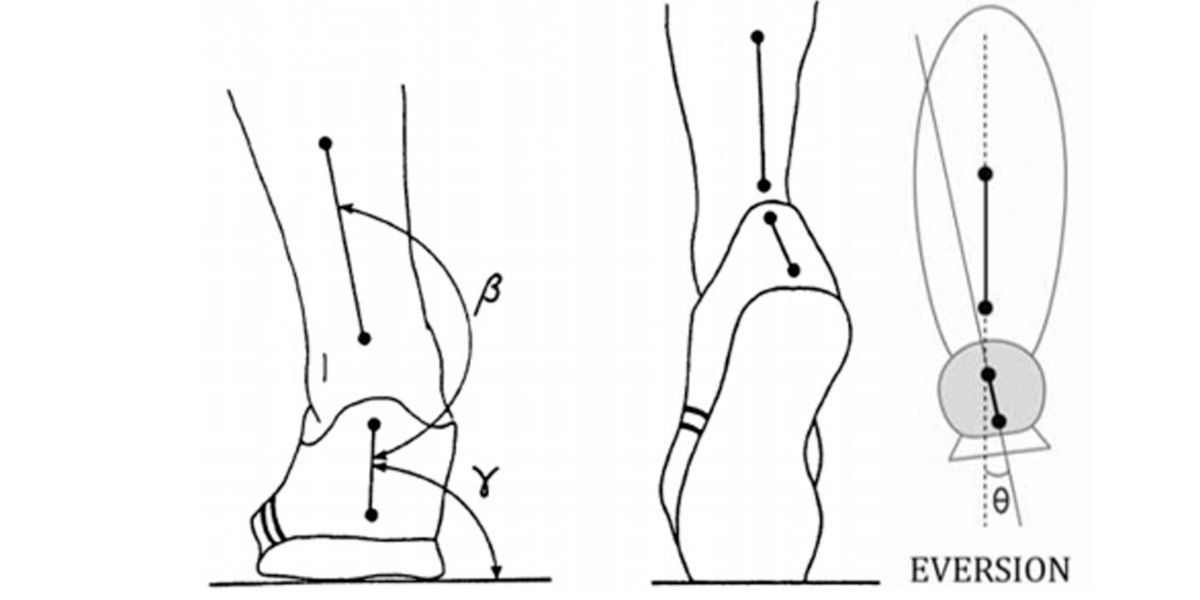

Uma má posição dos pés durante a locomoção pode causar alterações no joelho.

A principal causa conhecida através da qual os pés podem desenvolver o joelho de corredor, é a eversão da parte de trás do pé (pronação da planta do pé) que faz com que a tíbia gire internamente e que, ao mesmo tempo, faça com que o joelho fique para dentro (ou seja, se aproxime do eixo longitudinal do corpo) (Mo et al., 2013; Morley et al., 2010).

Figura VI. Representação gráfica da eversão na passada.